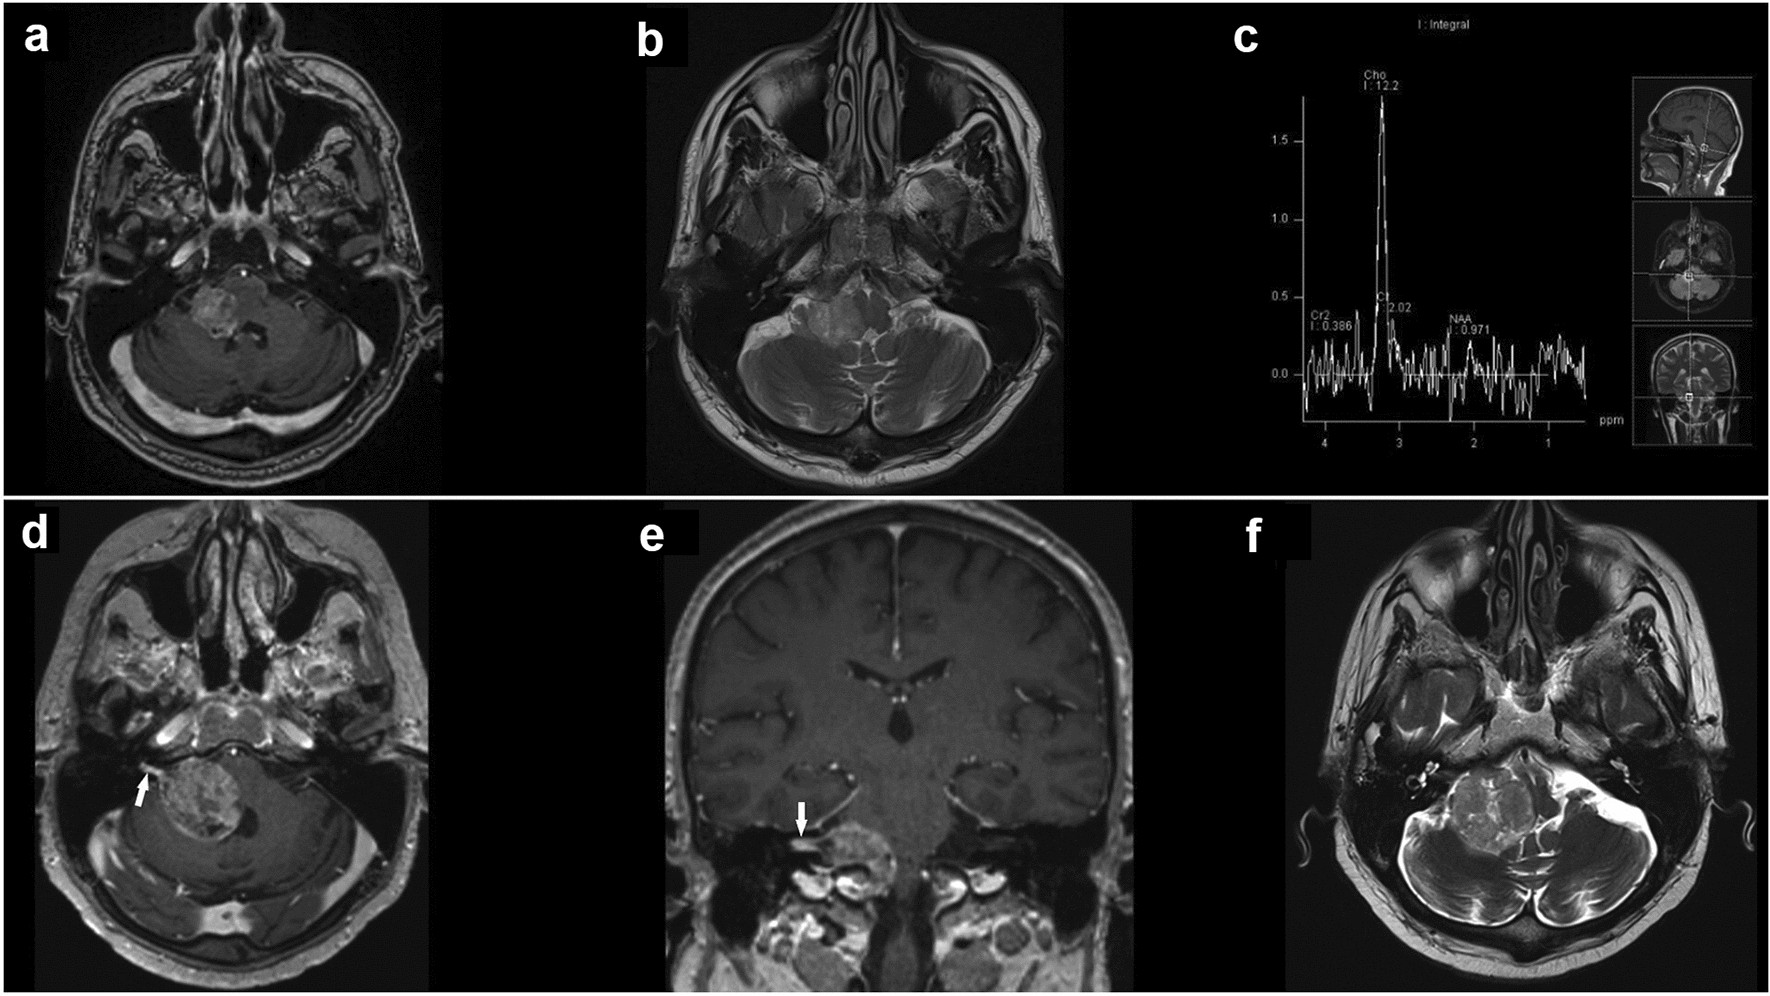

T1-weighted gadolinium-enhanced magnetization-prepared rapid gradient-echo MRI sequence of the brain in the axial plane (a) demonstrates a well-defined extraaxial solid mass of approximately 26 × 23 × 21 mm in the right CPA. T2-weighted MRI turbo spin-echo sequence of the brain in the axial plane (b) revealed peritumoral edema involving the right cerebellar peduncle and compressive effect on the brainstem, the fourth ventricle, and the right foramen of Luschka. Single-voxel MR spectroscopy of the CPA lesion (c) reveals elevated choline concentration, with no other metabolites. Follow-up T1-weighted gadolinium-enhanced MRI in the axial (d) and coronal planes (e) reveal marked enlargement of the tumor with extension to the IAC (arrow). Axial T2-weighted MRI (f) shows further expansion of the tumor mass to 35 × 34 × 33 mm and more pronounced compression on the lateral aspect of the brainstem and the fourth ventricle.